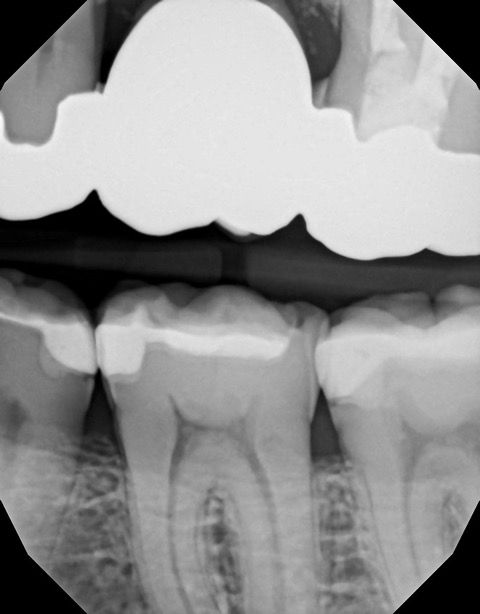

In my own practice, I compared two bitewings from the same patient, one taken with Acuity and one with our existing sensor, using identical exposure settings. The Acuity image immediately stood out. It showed noticeably sharper definition, cleaner contrast, and clearer interproximal visibility. The improvement was visible at a glance and reinforced the diagnostic advantages reported by our evaluators. This kind of image sharpness saves time and reduces retakes.